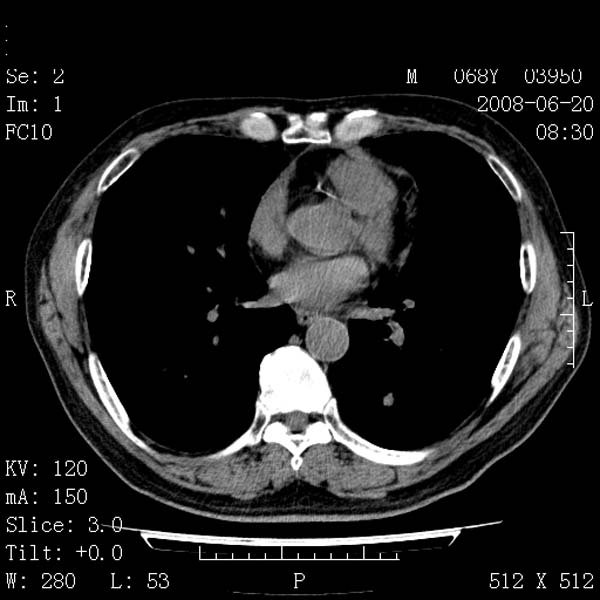

以下是引用守望可可西里在2008-6-24 1:11:00的发言:[br][br] 考虑为周围型肺癌:[br] 1.分叶结节,形态极不规则,蟹足样伸展的恶性浸润特征比较明确。[br] 2.磨玻璃影中由多个更高密度小结节聚集呈梅花瓣样。[br] 3.局部胸膜凹陷征比较明确。[br][br] 另:纵隔胸膜明显增厚、粘连。

以下是引用zjzjr在2008-6-24 11:19:00的发言:[br]支持左下肺周围型肺癌伴右肺转移,纵隔淋巴结转移,心包积液.

以下是引用zhangling在2008-6-24 14:56:00的发言:[br]我们科室意见报告为[br][br]1考虑左下肺周围型肺癌[br]2右肺小结节考虑转移瘤,纵隔淋巴结转移[br]3心包积液. [br] 各位老师分析的相当好 谢意[br]